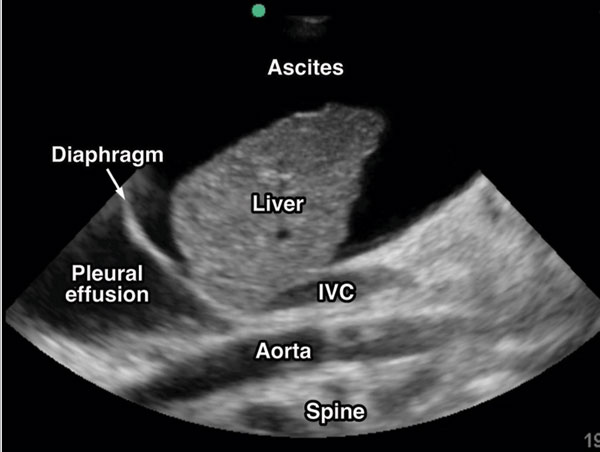

سونوگرافی از امواج صوتی با فرکانس بالا برای ایجاد تصویر داخلی اندامها استفاده میکند. این روش در بسیاری از بیماریها کاربرد دارد و برای کبد یکی از ابزارهای پایه و حیاتی است.

کاربردهای اصلی سونوگرافی کبد:

- بررسی اندازه و شکل کبد

- شناسایی تودهها و ندولهای مشکوک

- ارزیابی وضعیت سیروز یا کبد چرب

چگونه سونوگرافی تودهها و تغییرات خطرناک را نشان میدهد؟

سونوگرافی میتواند نشانههای زیر را شناسایی کند:

- وجود ندول یا توده: اندازه، شکل و محل توده قابل مشاهده است.

- تغییرات اکوی بافت: ناهمگونی یا افزایش/کاهش اکو ممکن است به معنای ضایعه یا سیروز باشد.

- تغییر در حجم یا شکل کبد: بزرگ شدن یا کوچک شدن بخشهایی از کبد هشداردهنده است.

- نشانههای غیرمستقیم سیروز یا فیبروز: مانند بافت ضخیم و ناهموار که زمینهساز سرطان است.